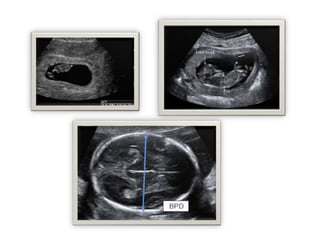

Done by doctor or the radiographer

 Booking ,dating, scan :

- 8-12 W

- Intrauterine pregnancy

- Viability

- Gestational age

- # fetus

 Anomaly sacn:

- At 22-24 w

 Growth scan:

- if indicated, high risk, localization of placenta, EFW, AFI,

presentation, etc

- At 36 W

Ultrasound in ANC